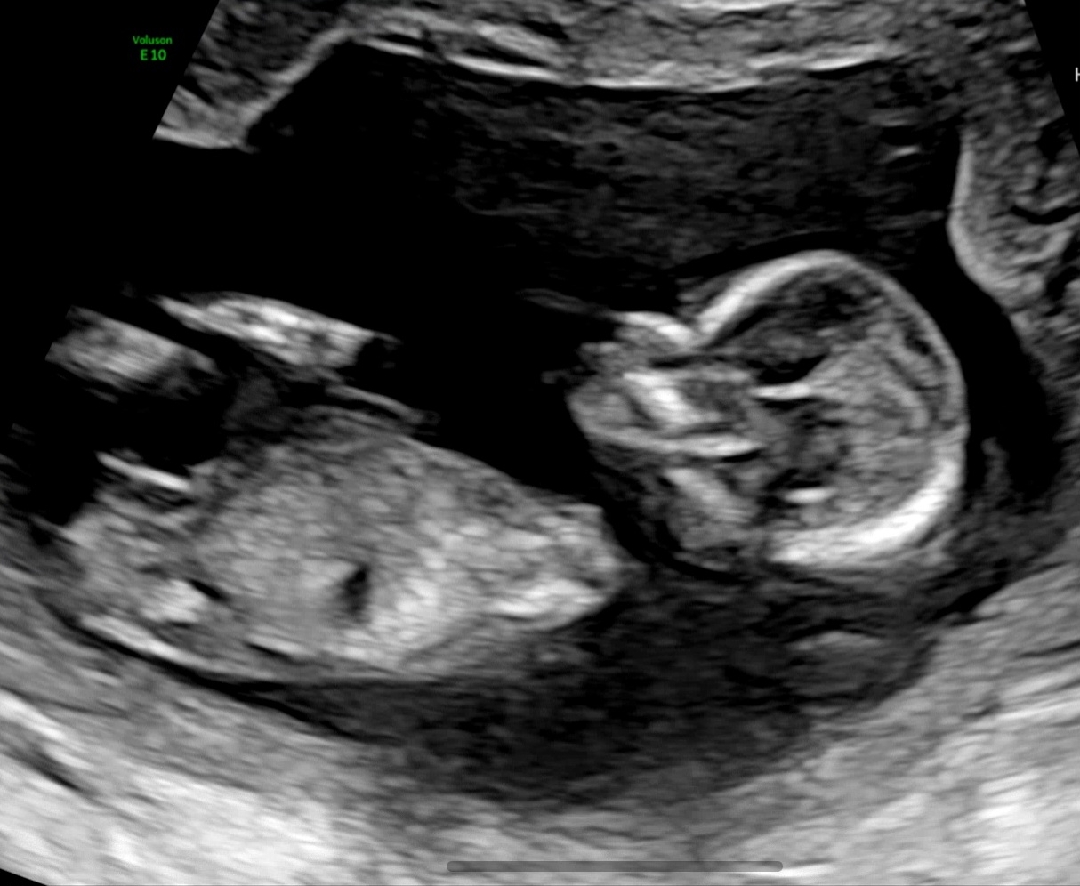

12주5일차 1차검사 통과!! 각도법?

1차 정밀검사 안전하게 통과했어요😆 성별 상관없이 건강만 하길 바라지만.. 한달 기다리기 너무 힘드네요....? 궁금해서 못참겠어요!! 도와주세요~~~